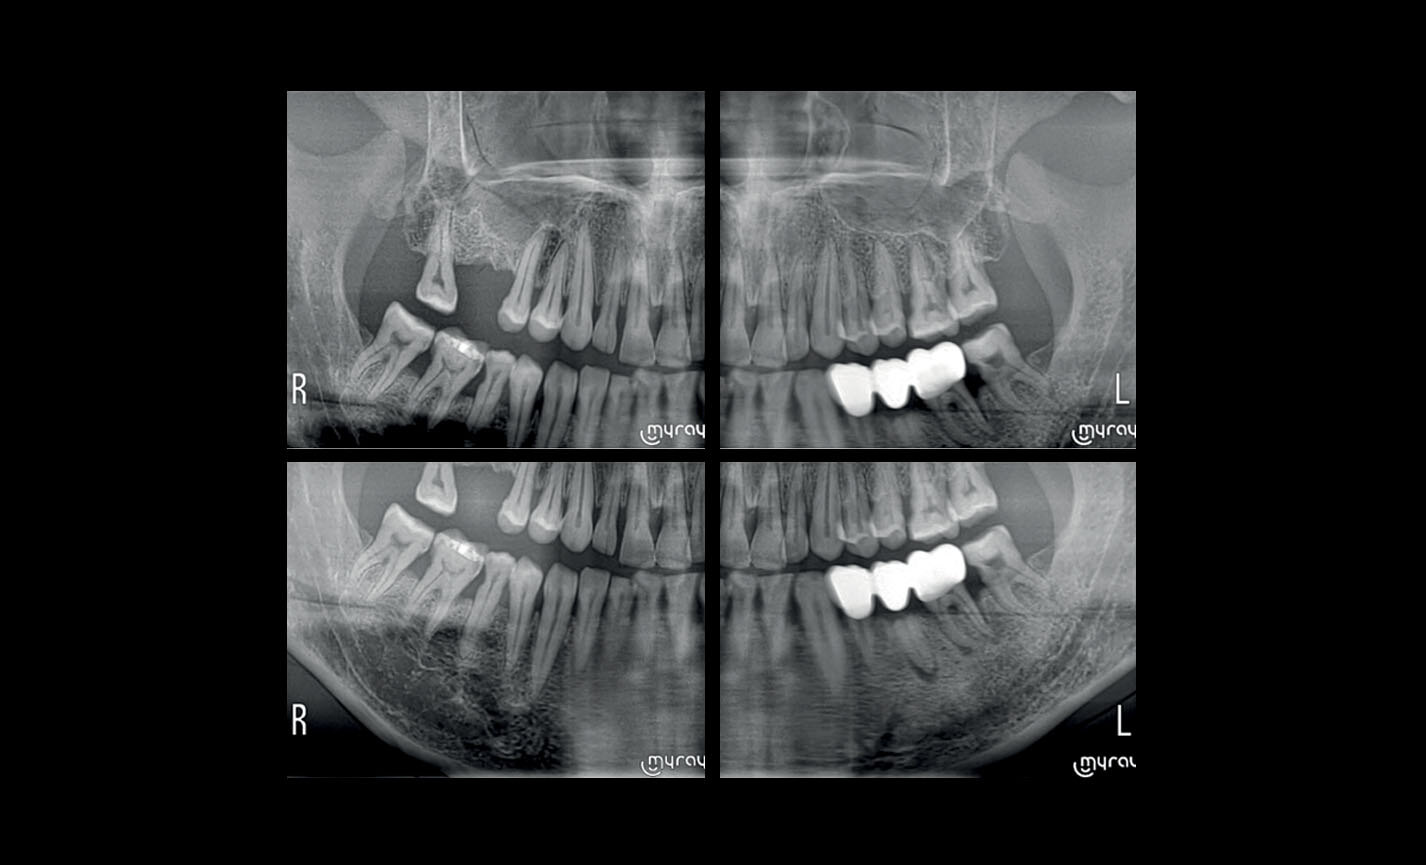

MULTIPAN SuperHD jusqu’à 11 couches

La technologie DCIII innovante - qui optimise la profondeur de foyer et augmente le niveau de contraste et, en conséquence, le pouvoir de résolution réel - permet d’obtenir un panoramique SuperHD à partir d’un ensemble de données extrêmement vaste, pour obtenir un MultiPAN à 11 couches. Particulièrement utile en cas de morphologies complexes.

Orthopanoramiques

Panoramique orthogonal : minimise les superpositions d’éléments dentaires adjacents pour une meilleure analyse parodontale.

Orthopanoramiques

Panoramique rapide : dose faible et temps de balayage réduit, idéal pour des investigations primaires, le suivi, ou en cas de patients non collaborants.

Orthopanoramiques

Panoramique enfant : exposition limitée et paramètres optimisés pour une investigation pédiatrique rapide.

Orthopanoramiques

Dentition complète à quadrants : investigations localisées avec segmentation sélectionnable pour limiter la dose d’irradiation.

Orthopanoramiques

Projections bitewing, investigation limitée aux couronnes : haute résolution et faible dose, une alternative valable aux images intra-orales en cas de patients avec un fort réflexe de rejet.